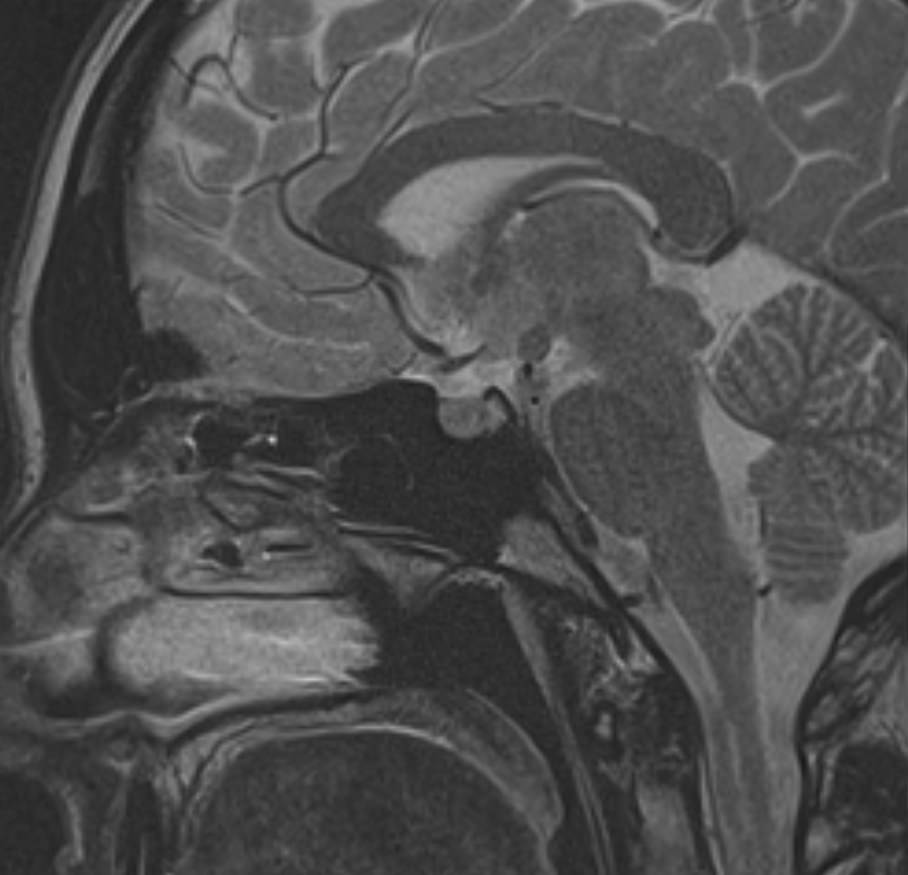

Поскольку гипофиз имеет очень маленькие размеры и расположен в глубине головы, досконально изучить его структуру можно только с помощью МРТ. Ни один другой из существующих методов визуализации не способен дать настолько четкие изображения и данные о состоянии гипофиза. Расшифровка результатов выполняется рентгенологом.

С помощью МРТ гипофиза можно создать его трехмерное изображение с высокой степенью детализации. Это позволяет обнаружить патологические изменения на самых ранних этапах, начиная от аномалий развития, сосудистых нарушений, воспалительных процессов и заканчивая опухолями разной природы.

МРТ гипофиза выполняется в нашей клинике выполняеется только с контрастным усилением, что повышает четкость получаемых изображений, а по особенностям распределения контрастного препарата в тканях можно с высокой точностью не только обнаружить доброкачественные и злокачественные опухоли, но и исследовать их локализацию, структуру, определить границы и заметить метастазы.

Чаще всего исследование проводится для диагностирования аденомы гипофиза и определения ее величины: микроаденомы (до 10 мм), макроаденомы (10—30 мм) и гигантской аденомы (более 30 мм). Также с его помощью обнаруживается неоднородностьструктуры, асимметрия границ, изменения положения воронки гипофиза и ее строения, а также деформации окружающих костных тканей.